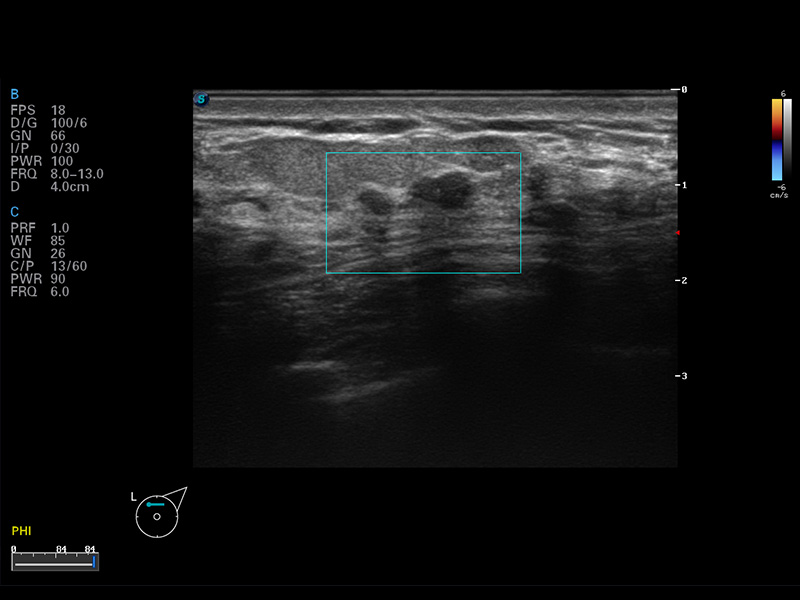

S8 EXP便携式彩色多普勒超声诊断仪是诸侯快讯官网研发的高端全身应用型便携彩超。高通道的VIS平台融合可视化(Visual)、智能化(Intelligent)和人性化(Smart)的特点,配以诸侯快讯官网自主研发生产的探头大家族,使您能够快速、准确的获得病人信息,提高工作效率的同时减轻疲劳。

μ-Scan微米成像

谐波成像

空间复合成像